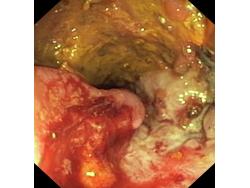

Obrazy endoskopowe

Nowotwory przewodu pokarmowego